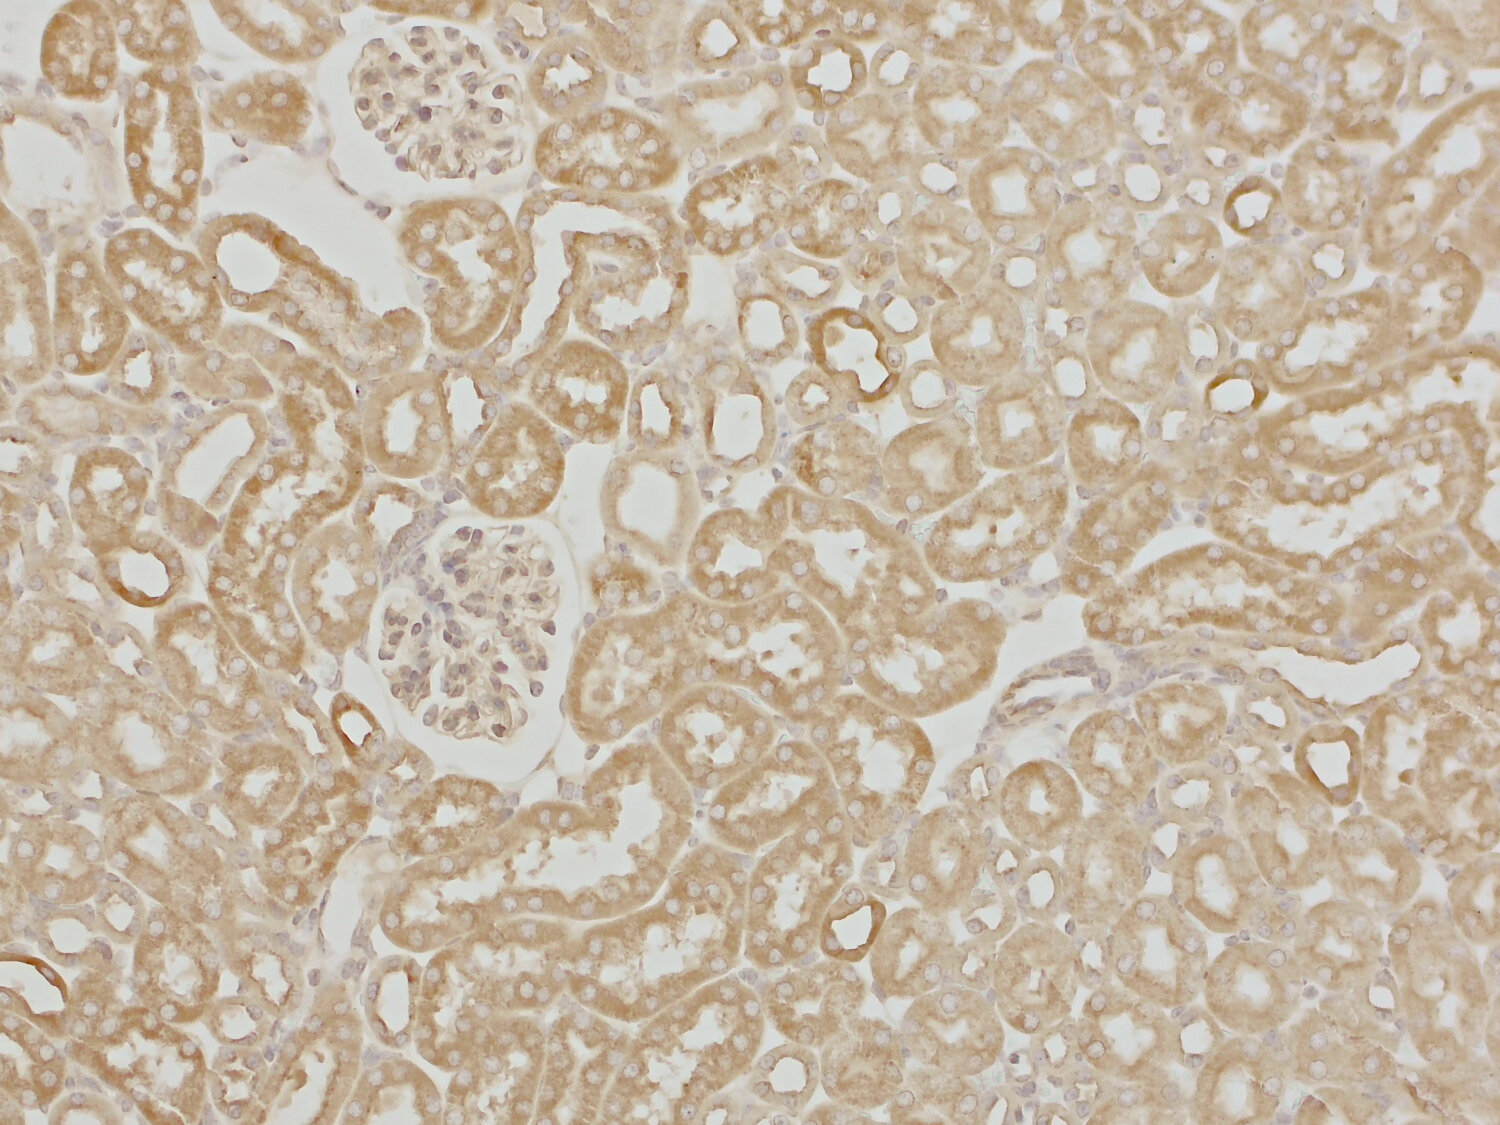

IHC-P (FFPE): 1 : 1000 (see remarks) gallery

IHC-P (FFPE): Antigen retrieval with Tris-EDTA buffer pH 9 is recommended for chromogenic detection.

For chromogenic detection, an optimized AGR time of 20 minutes is recommended for best results.

Detection of Cortactin in a formalin fixed paraffin embedded (FFPE) human colon section